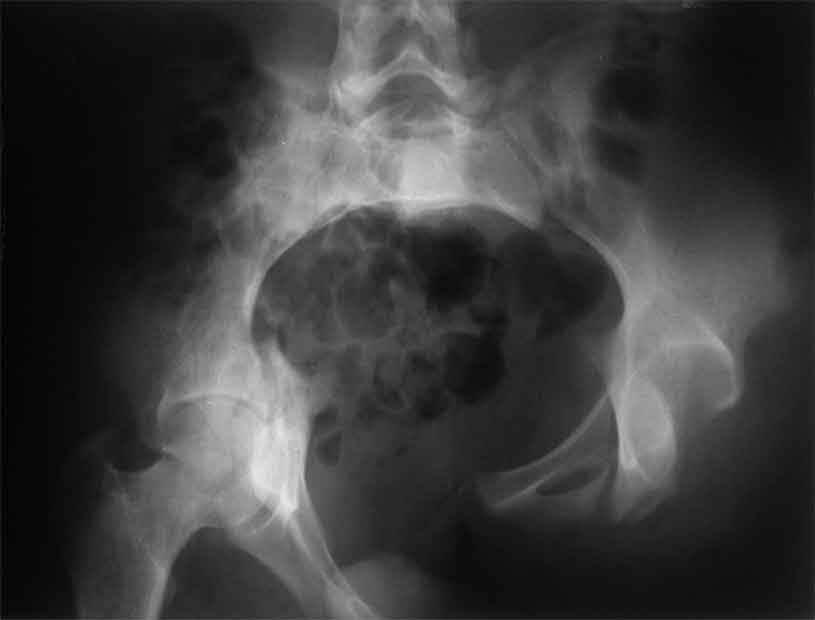

Уважаемые коллеги, сложный случай, интересует ваше мнение. Травма 2 месяца назад, в результате ДТП. При поступлении в лечебное учреждение по м/ж выполнено формирование культи на уровне в/3 левого бедра по (травматический дефект левой н/конечности), в послеоперационном периоде раневая инфекция, остеомиелит - экзартикуляция.

Повреждение таза лечилось консервативно. Интересует ваше мнение по поводу тактики лечения, попытаться свести аппаратом, а потом открытый этап (каким доступом/доступами)? другие варианты? С уважением Максим Агалаков